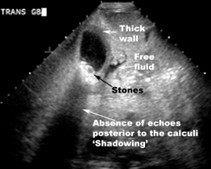

- Ultrasound abdomen showed multiple, gallbladder calculi, thickened GB wall and pericholcystic fluid.

According to Tokyo guidelines, the patient was diagnosed with mild acute calculous cholecystitis based on clinical findings, supportive laboratory findings and characteristic radiological findings.